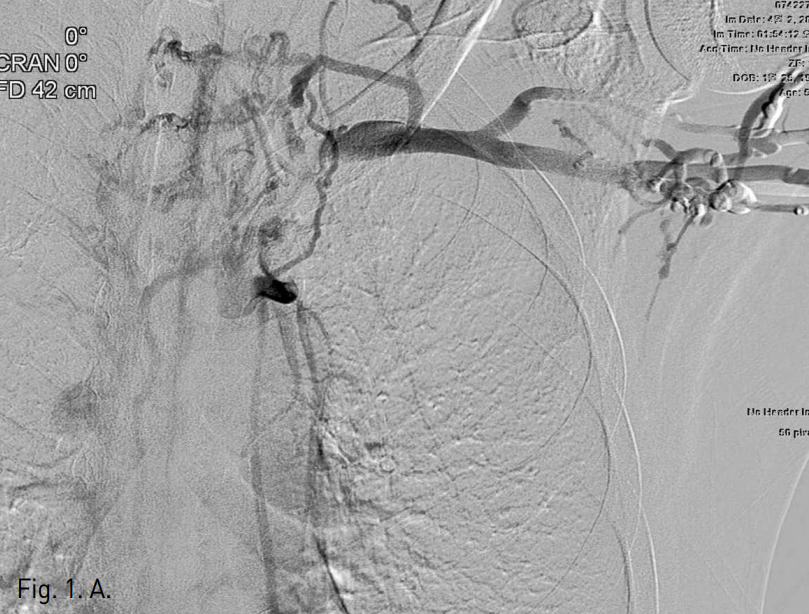

양측 상지정맥 천자 후 시행한 중심정맥조영술 사진에서 양측 쇄골하정맥부터 양측 중심정맥의 완전 폐색이 관찰되었으며, 우측 상지의 혈류가 우측 외흉정맥(lateral thoracic vein), 늑간정맥, 기정맥 (azygos vein)을 순차적으로 통해 심장으로 유입되고 있었음 (Fig. 1).

Fig. 1

Both central venograms obtained with injection of contrast medium via both arm veins (A: left, B: right) show complete obstruction of right distal and left proximal subclavian veins with non-visualization of more central veins. The venous blood flow from right upper extremity drains into the heart via collaterals of right lateral thoracic (arrows), intercostal, azygos veins.